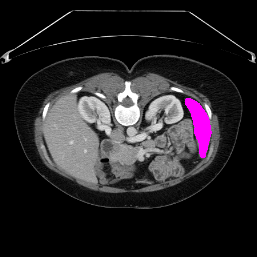

In order to assess the performance of the proposed method, we compare the performance of the proposed model with excellent models in recent years. Table 1 and Table 2 shows the comparison results of different models in setting1, while Table 3 and Table 4 shows the comparison results of different models in setting2 on the data set in recent years. PANet[25] is the most widely influential few-shot model in the field of few-shot image segmentation on natural images. SENet [18] is the first few-shot segmentation model proposed for medical images. SSL-ALPNet[19] introduced the milestone of using superpixel self-supervision to train few-shot medical image models. RPNet[29] is a supervised method with a recursive mask optimization module to iteratively optimize the segmentation mask, [27] adapt it into the same self-supervision learning framework and applies setting1 to it and denoted as SSL-RPNet; CRAPNet[27] is the latest SOTA model for 2023. Compared with CRAPNet, our method outperforms most of the state-of-the-art models and only slightly outperforms CRAPNet. Figures 3 and 4 show examples of the model’s segmentation predictions on different datasets, respectively; The first row is the support map, the second row is the label map, and the third row is the segmentation prediction of the model.